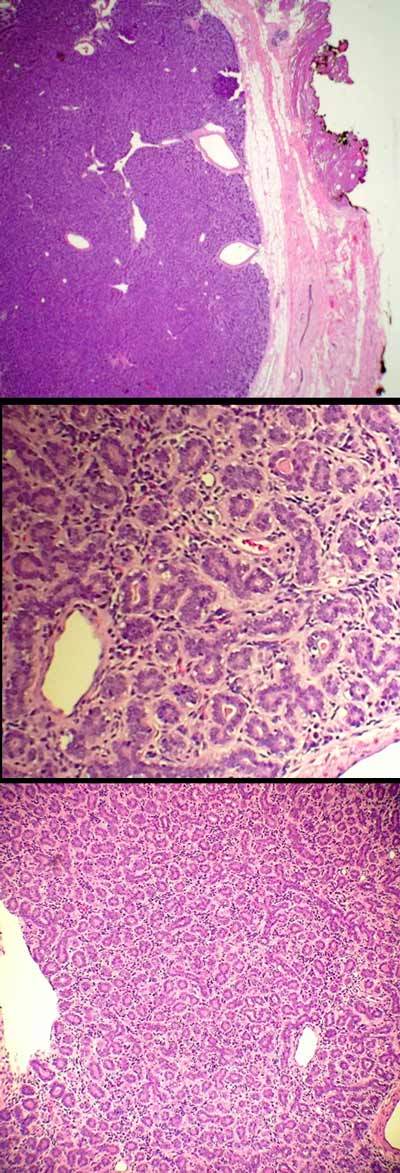

Adenoid cystic carcinoma (ACC) of the breast